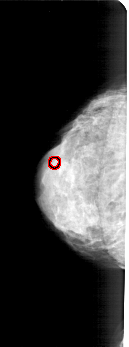

FILE: A_1775_1.LEFT_CC.OVERLAY

TOTAL_ABNORMALITIES 1

ABNORMALITY 1

LESION_TYPE CALCIFICATION TYPE PLEOMORPHIC DISTRIBUTION CLUSTERED

ASSESSMENT 4

SUBTLETY 1

PATHOLOGY BENIGN

TOTAL_OUTLINES 1

BOUNDARY